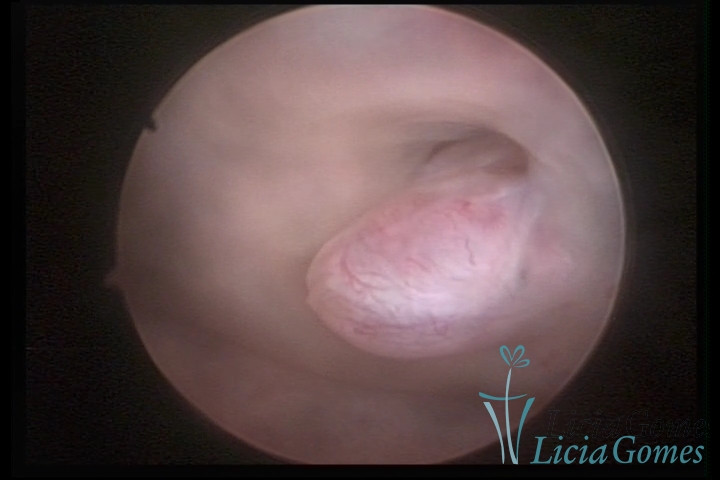

ENDOCERVICAL POLYPS

Benign tumors resulting from the reactive focal proliferation to inflammatory processes or hyperestrogenism situations, which may be sessile (with a large implantation) or stalked.